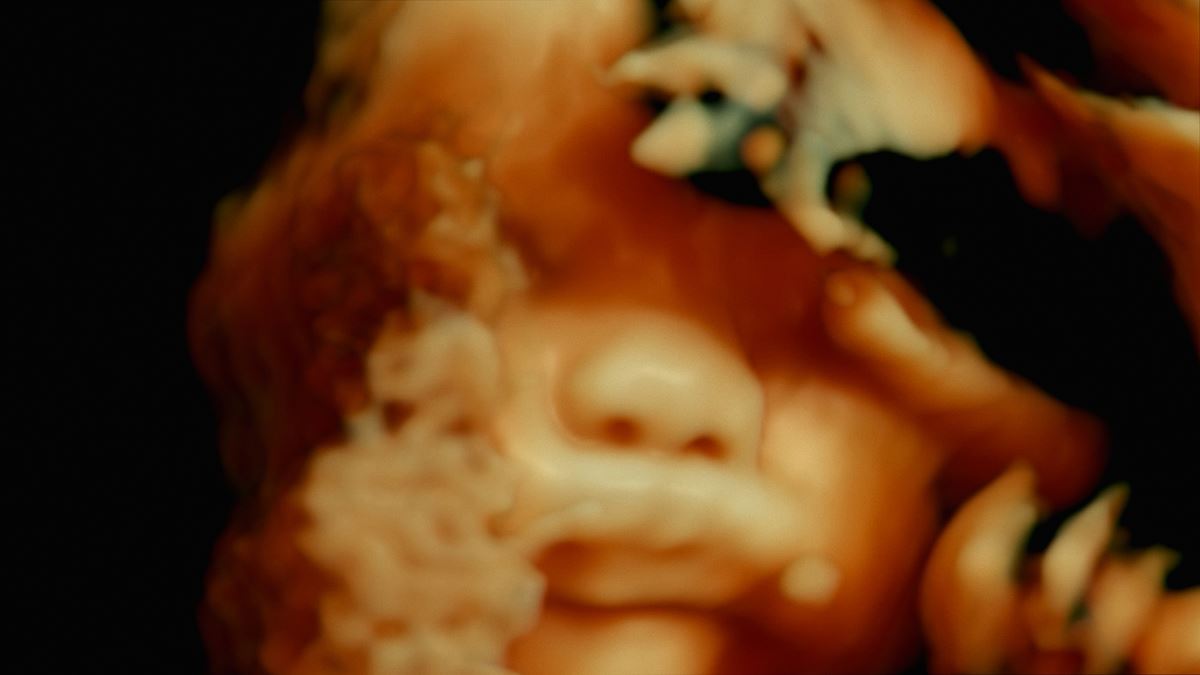

『人体の構造について(原題)』予告